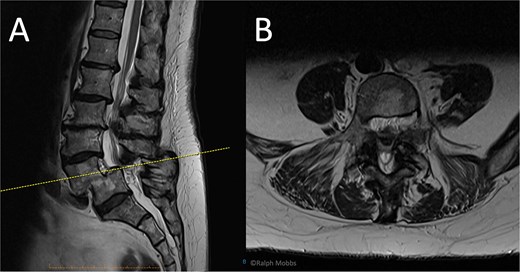

Standing radiographs and magnetic resonance imaging (MRI) demonstrated stable Grade-II L5/S1 degenerative spondylolisthesis with severe bilateral foraminal and lateral-recess stenosis compressing the exiting L5 and traversing S1 roots (Fig. 1). Computed tomography (CT) confirmed intact pars and severe facet arthropathy. Because open decompression/fusion was judged high risk due to significant comorbidities, uniportal full-endoscopic decompression alone under conscious sedation was offered.

Preoperative and intraoperative imaging of case 1. (A) Sagittal T2-weighted MRI demonstrating grade II degenerative spondylolisthesis at the L5/S1 level. (B) Axial T2-weighted MRI. (C–F) intraoperative fluoroscopic views illustrating the placement of the working channel and guidewire.

The operation was performed with patient in the prone position with free abdominal pressure. A skin incision was made positioned just lateral to the midline spinous process at the targeted lumbar interspace. Under fluoroscopic visualization, a series of dilators were advanced through the paraspinal muscles to the lamina, establishing a uniportal working channel (Elliquence, USA) for the endoscopic system with constant irrigation (Fig. 1). Hypertrophied ipsilateral ligamentum flavum and a portion of the ipsilateral facet joint were removed with radiofrequency probe, Kerrison rongeur and grasping forceps, preserving the majority of the facet joint on the approach side.